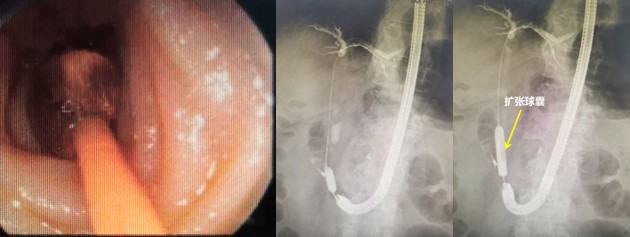

赵刚副主任凭借丰富的经验和精湛的技术,运用胃镜佩戴透明帽顺利找到前期设定的钛夹标记及十二指肠主乳头,然后利用专业器械,在内镜精细操作下,成功进行乳头括约肌切开及球囊扩张术,并最终将胆管内结石顺利取出。整个操作用时不到20分钟。

毕Ⅱ式胃大部切除术后的ERCP操作难度比普通ERCP超出很多,首先就是内镜的选择,按照《中国ERCP指南(2018版)》的建议,推荐首选十二指肠镜进行操作,但十二指肠镜在进镜操作以及寻找输入袢和十二指肠乳头方面明显不如直视镜。消化内科团队通过前期数年来的工作积累,制定了毕Ⅱ式胃大部切除术后ERCP操作的“交大二附院流程”,那就是先进行胃镜检查,由操作者亲自确认术式、输入袢肠管的走行以及十二指肠主乳头的位置,同时在内镜下对乳头进行定位标记,另外,对于输入袢开口较为隐蔽或内镜通过输入袢口较为困难的病例,操作者也会在输入袢口处额外进行标记,以便于后续ERCP操作时的二次寻找。在手术操作过程中,消化内科ERCP团队一般都会选用胃镜佩戴透明帽进行操作,透明帽一方面有利于进镜寻找目标肠袢,另一方面也可提高乳头插管时的镜身稳定性。